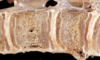

Cervical vertebral myelopathy "Wobbler syndrome"

Cervical vertebral malformation-malarticulation in a horse. Flexion of the cervical vertebrae results in stenosis of the spinal canal (asterisk). Flaring of caudal epiphysis (arrowhead), can also contribute to spinal compression

Cervical vertebral malformation-matriculation in a horse, Osteochondrosis of the articular facet joints can contribute to the intervertebral joint instability